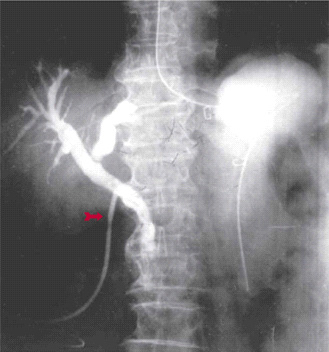

Endoscopic retrograde cholangio pancreatography (ERCP) בשיטה זו מחדירים אנדוסקופ דרך הפה לתריסריון, מזהים את הפפילה על-שם ואטר, ולתוכה מחדירים צנתר שדרכו מזריקים חומר ניגוד לדרכי המרה וללבלב. ההדגמה היא רנטגנית וניתן לראות בה הרחבה של דרכי המרה, אבנים בדרכי המרה (תצלום 30.8) ועוד.

| תצלום 30.8: הדגמת אבנים בדרכי המרה ב- ERCP (חיצים מצביעים על אבנים בדרכי המרה, חץ מקווקו על אבנים בכיס המרה). | |